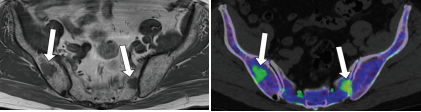

双能量骨髓水肿:舟状骨

评估骨髓浸润活性